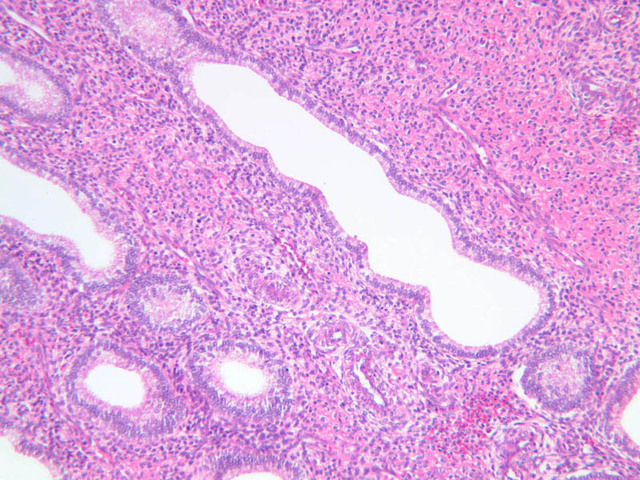

The menstrual phase lasts 1 -5 days, and corresponds to ovarian menstrual phase; i.e., degeneration of corpus luteum with consequent decrease in estrogen and progesterone levels. During this phase the functionalis sloughs off leaving the basalis. Just prior to sloughing, the glands are extremely dilated and tortuous.

This phase occurs on days 15 to 27 and corresponds to the ovarian luteal phase characterized by rising levels of progesterone. The epithelial cells begin to secrete a mucoid fluid rich in nutrients, especially glycogen. The glands become highly coiled and folded and toward the end, very distended. The density of the stroma lessens as it becomes edematous. (slides B-99 [2.5x, 10x, 20x, 40x] [2.5x, 10x, 20x, 40x]; B-100 [1x, 2.5x] [2.5x, 10x, 20x, 40x] [2.5x, 10x, 20x, 40x])